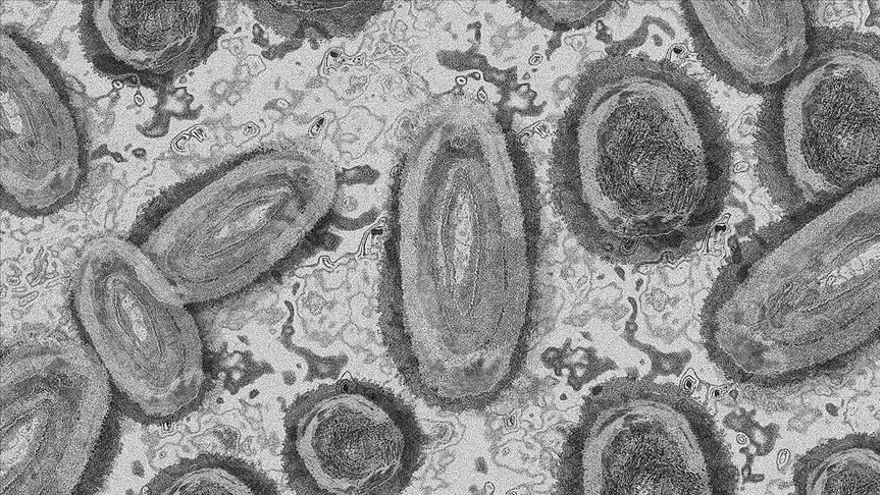

M-Çiçeği, Poxviridae ailesindeki Orthopoxvirus cinsinin bir üyesi olan M-Çiçeği virüsünün (MPox) neden olduğu bir hastalıktır. Orthopoxvirus cinsinin diğer üyeleri Camelpox, Cowpox gibi diğer canlı türlerinde de görülebilen zoonotik virüslerdir. Aynı ailenin insana özgü türü olan ve genel olarak bilinen ismi ile çiçek hastalığına neden olan Variola virüsü, etkin aşılama ile 1980 yılında dünya üzerinden eradike edilmiştir.